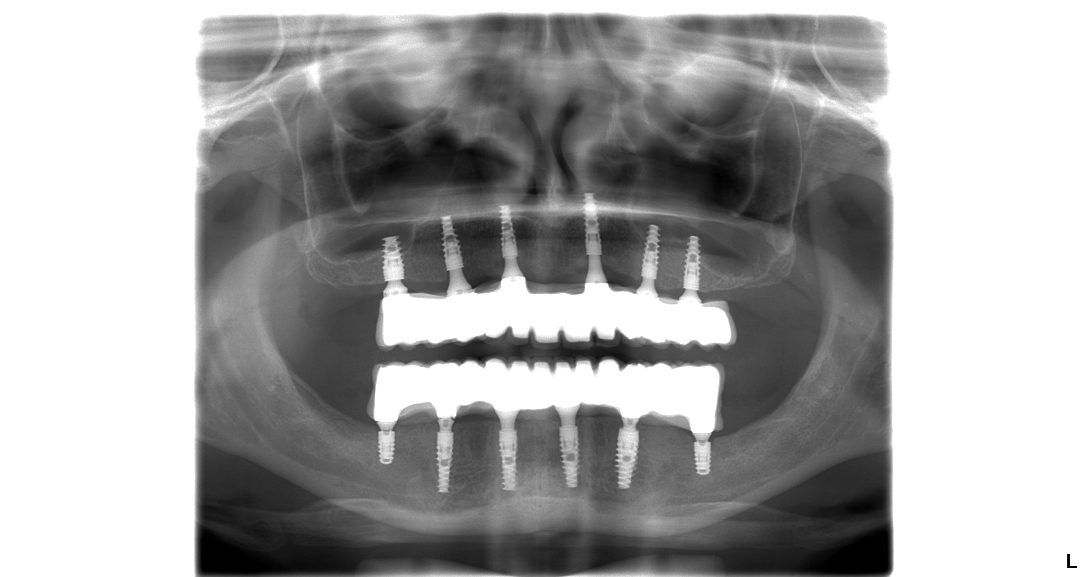

Pacientka Eva podstúpila implantáciu hornej a aj spodnej čeľuste v celkovej narkóze. Vo vrchnej čeľusti pacientka nosila snímateľnú protézu, ktorá vzhľadom na jej vek nebola dobrým riešením. Preto sa rozhodla pre radikálnu zmenu. A ako napísala v dotazníku po ošetrení bola veľmi spokojná s finálnym výsledkom.

Hneď po implantácii sa pacientovi nasádza na zavedené implantáty dočasný zubný mostík, ktorý sa fixne pripevní k implantátom. Dočasný zubný mostík je spevnený titánovou konštrukciou pre maximálnu trvácnosť a stabilitu.